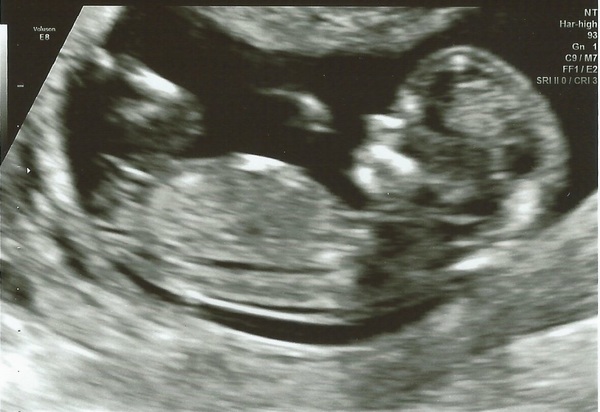

becciandbump · 31/05/2016 21:09

Not sure how to post the link but having a go guys

Insertwitticismhere · 01/06/2016 11:56

Hi all - wow these December babies threads move fast! I posted on the first but have been lurking since. I've had 2 bouts of nasty tonsillitis and was convinced a raging temp and all the antibiotics would have done the baby no good. 12 week scan today though and so far so good! Due date of 11th Dec!

Insertwitticismhere glad to hear you're feeling better after tonsillitis, it is very nasty, I didn't realise til dd1 had it last year and at night she'd struggle to breath, hopefully you won't suffer with it again! Lovely scan picture.

Beautiful scan insert!

Hi girls, Had scan this morning, unforch my sonographer lady was right moody moose! But just glad I saw baby and heartbeat (albeit very briefly) My scan picture is terrible too baby was upside down and wouldn't budge!! It also looks very squished up :/ Bit pissed off it wasn't a lovely experience but I guess it was in some was because babe is all ok :) Also dates have been brought forward again so I'm due on the 5th too Azure83 Thanks Eskerina81 think I'll just have to wait....... :)